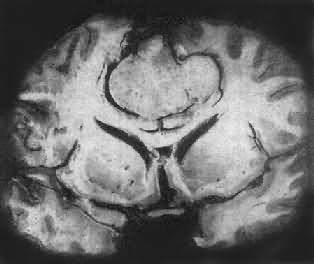

图16-23 星形胶质细胞瘤 左大脑半球肿胀,肿瘤边界不清,部分呈胶冻状 镜下,肿瘤细胞形态多样,可相似于纤维型星形胶质细胞、原浆型星形胶质细胞和肥胖星形胶质细胞,故分别称为纤维型、原浆型和肥胖型星形胶质细胞瘤。前二者为良性肿瘤,后者性质介于良恶性之间。如肿瘤细胞出现间变,细胞密度增大,异型性明显,核深染,出现核分裂像,毛细血管内皮细胞增生,则为间变性星形胶质细胞瘤,为恶性肿瘤。 高度恶性的星形胶质细胞瘤称为多形性胶质母细胞瘤(glioblastoma multiforme),多见于成人。肿瘤好发于额叶、颞叶白质,浸润范围广,常可穿过胼胝体到对侧,呈蝴蝶状生长(图16-24)。瘤体因常有出血坏死而呈红褐色。镜下,细胞密集,异型性明显,可见怪异的单核或多核瘤巨细胞。出血坏死明显,是其区别于间变性星形胶质细胞瘤的特征。毛细血管明显增生,内皮细胞增生、肿大,可导致管腔闭塞和血栓形成。肿瘤发展迅速,预后极差,患者多在2年内死亡。